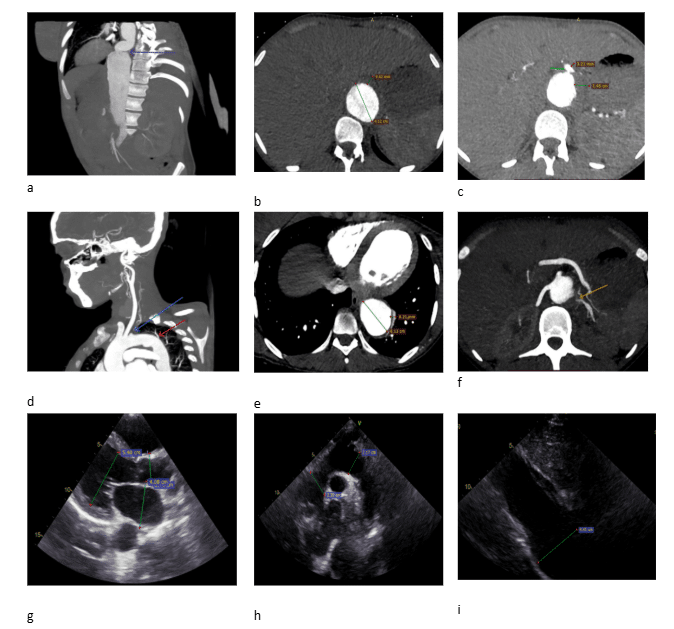

There was diffuse thickening of the aortic arch and descending thoracic aorta, with significant stenosis of the brachiocephalic and subclavian arteries on thoracic aortography and circumferential mural thickening and focal narrowing of the abdominal aorta, including the renal and celiac arteries on abdominal angiography (Figure 1). The echocardiogram shows that the Left-sided cardiac chambers were dilated, with global systolic dysfunction of the left ventricle, with an estimated EF of 30-35%, and moderate functional mitral regurgitation was also noted (Figure 1).

Figure a: Abdominal computed tomography (CT) angiography with sagittal section shows abdominal aorta with tortuosity (violet arrow)

Figure b: Abdominal CT angiography transverse section at kidney level, there is maximum dilatation of the abdominal aorta measuring 4.12cm with circumferential mural thickness of 3.84 mm with intimal irregularity.

Figure c: Abdominal CT angiography transverse section at celiac artery origin shows focal narrowing of celiac artery (green arrow) with circumferential thickening

Figure d: Sagittal section of CT angiography of upper extremity and aortography shows diffuse focal circumferential thickening of the thoracic aorta extending to the brachiocephalic trunk with luminal stenosis of the subclavian arteries (blue arrow) and tortuosity of the thoracic aorta (red arrow)

Figure e: Transverse section at heart level shows enlarged thoracic aorta with focal wall thickening

Figure f: Abdominal CT angiography transverse section at the level of renal artery origin shows decreased left renal artery caliber in the proximal 1/3 of the artery (yellow arrow)

Figure g: 2-dimensional (2D) Transthoracic Echo (TTE) on long axis shows dilated left atrium, left ventricle, and aorta at the aortic sinus during diastole

Figure h: 2D TTE suprasternal notch view shows normal measurement

Figure i: 2D TTE on subxiphoidal and inferior vena cava (IVC) view shows dilated abdominal aorta measuring 4.4cm